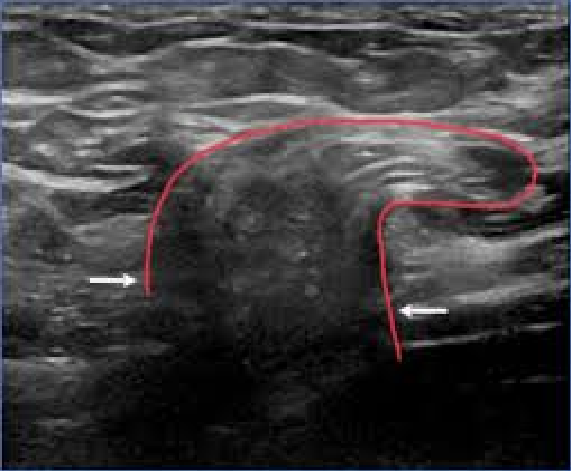

Ecografia de caderas

Estudio esencial en bebés para detectar displasia del desarrollo de cadera. Es indolora y se realiza idealmente en los primeros meses de vida como parte del control del niño sano.